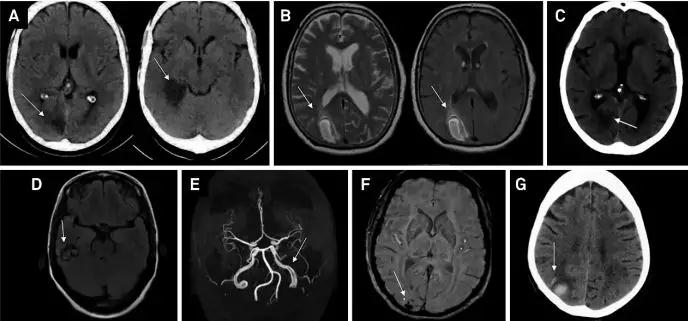

目前在医学文献中,关于“爱丽丝梦游仙境综合征”的病例报道不到200例,报道了患者脑部图像的更是少之又少,但依然可以看到如下的一些病例图片。

从这些图像可以发现,与“爱丽丝梦游仙境综合征”相关的血管病变主要发生在右侧枕叶区域,其中有一位患者的“爱丽丝梦游仙境综合征”来源于颞叶海绵体瘤。

经脑功能成像研究发现,“爱丽丝梦游仙境综合征”主要与初级视觉皮层、纹外皮层和顶叶皮层的异常活动有关。甚至额叶典型也可能与“爱丽丝梦游仙境综合征”有关。虽然大多数病变位于右脑,但并不一定都在右脑。